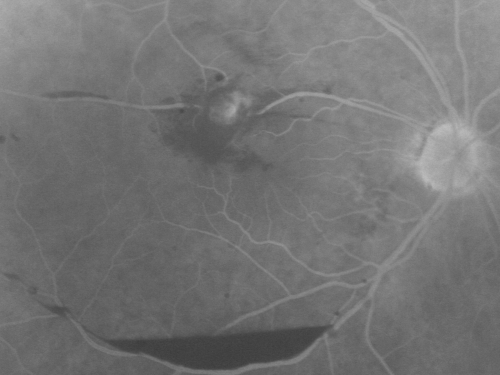

Retinal Arterial Macroaneurysm - Increased Swelling after Laser

March 21, 2011.  This pleasant 66-year-old woman had laser to retinal arterial microaneurysm in the right eye January 12th.  Her vision was getting better, but now it is worse the last few days.  She is at home taking care of her demented mother and she and her sister lift her mother a fare amount of the time.  I also checked her blood pressure, which was 120/65.  VISUAL ACUITY:  OD 20/200